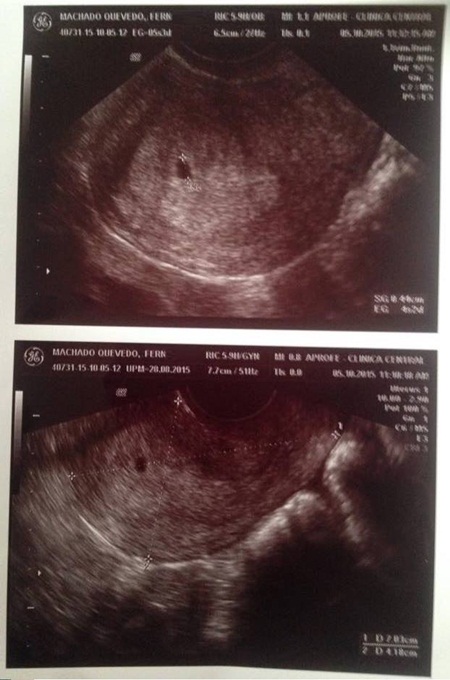

จนกระทั่ง ไดแอนได้ประกาศให้โลกออนไลน์รู้ว่า เฟอร์นานโด แฟนหนุ่มของเธอ กำลังตั้งท้องได้ 4 เดือนแล้ว แม้ว่าทั้งคู่จะดูเหมือนเป็นชายและหญิงข้ามเพศร้อยเปอร์เซ็นต์ แต่แท้จริงแล้วทั้งคู่ยังไม่ได้ผ่าตัดแปลงเพศ นั่นหมายความว่าอวัยวะสืบพันธุ์ของทั้งคู่ยังเป็นปกติเช่นเดิม จึงทำให้การตั้งครรภ์นี้เกิดขึ้นจากวิธีตามธรรมชาติอย่างสมบูรณ์